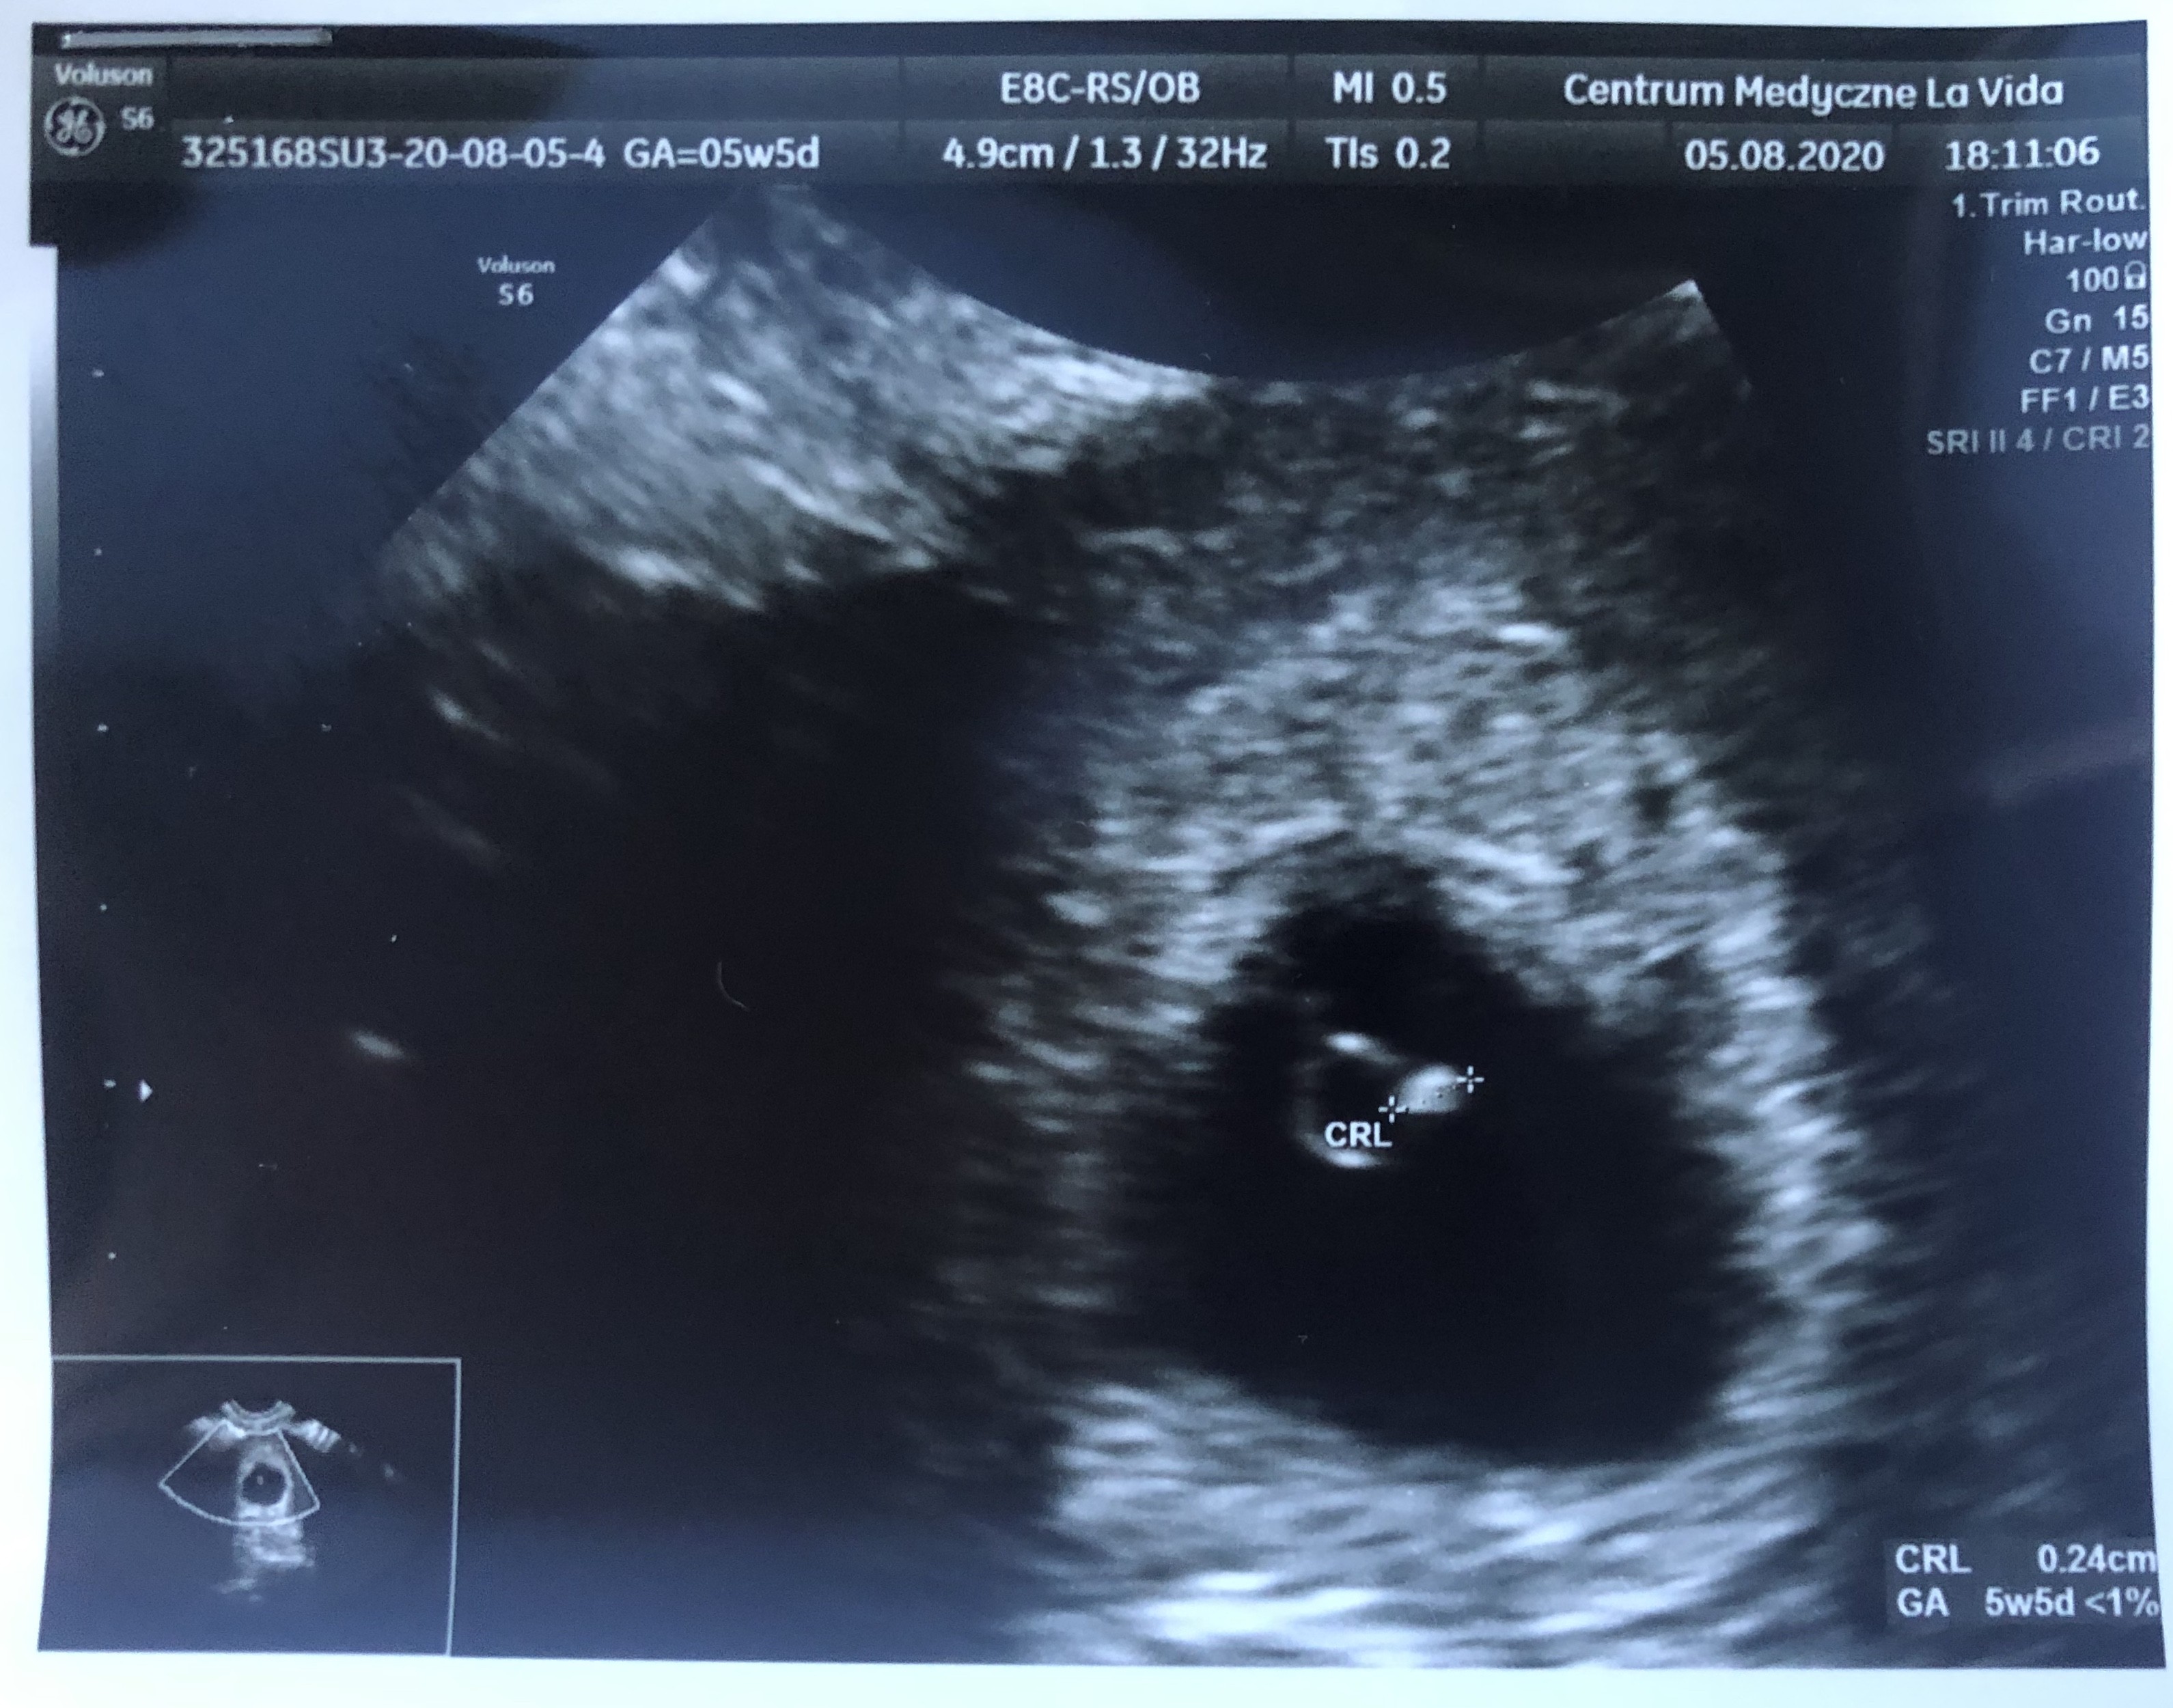

Gratulacje i wszystkiego dobrego dla wasDziewczyny ja już po wizycie po pierwszym USG!

Wszystko jest na miejscu, widać pęcherzyk, ciałko żółte i już nawet zaczęła się akcja bicia serduszka ❣ Nie słyszałam, ale widziałam na USGjejuuu mega się ekscytuje tym bardziej, że to moja pierwsza ciąża, dalej w to niedowierzam

U mnie jest 5+5 dni i termin wypada na 02.04 czyli tak jak w appce

Kolejna wizyta pójdę 02.09 robiąc wcześniej badania krwi

Ale się cieszę!